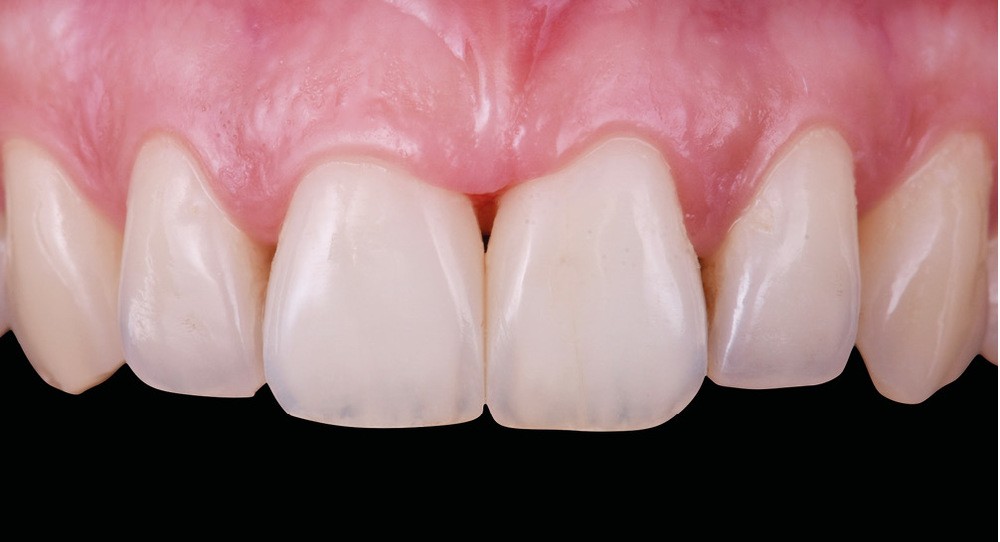

Si les techniques de reconstruction papillaire présentent des résultats non prédictibles, les facettes céramiques peuvent être une réponse fiable au problème des triangles noirs mais imposent une préparation plus marquée. En effet, pour obtenir un profil d’émergence adéquat et une bonne fermeture de l’espace interproximal, il faut préparer les surfaces de contact et venir chercher la ligne de transition palatine, obligeant à retirer une quantité de tissu sain non négligeable.

La fermeture des triangles noirs en technique directe avec des résines composites offre une alternative très favorable avec une approche non invasive, esthétique, un coût réduit et une possibilité de réintervention aisée. Plusieurs méthodes ont été proposées : réalisation à main levée sans matrice (à proscrire), avec bande de matrice transparente plate ou galbée, avec matrice postérieure customisée et utilisée verticalement… Il faut bien comprendre qu’aucun coin en bois ou plastique ne pourra être employé pour stabiliser cette matrice, car il empêcherait la création d’un profil d’émergence anatomique convexe en induisant une déformation concave de la matrice à sa base.